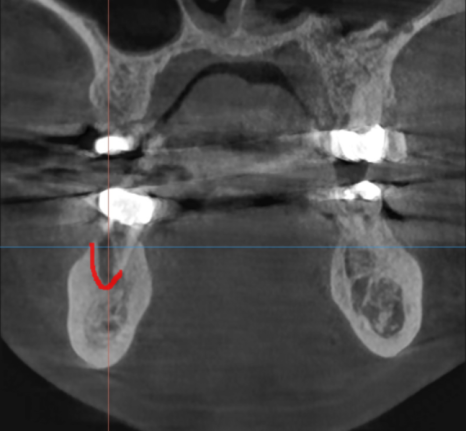

ct를 찍어 얼마나 잇몸뼈가 녹았는지

상태를 보았는데요.

하얗게 차 있어야할 부위가

까맣네요.

염증 지독한 것이

뿌리 모양까지 변화시켰네요.

이전 사진에 비하여 약간 짧아진 게

뿌리까지 흡수되었습니다.